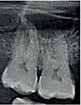

The Dental Panoramic Tomogram (DPT) confirmed the presence of all permanent teeth including the developing third molars (Figure 3). Root morphology appeared normal. The upper right central incisor had a root canal filling. The upper standard occlusal

radiograph revealed that the upper right central incisor had an adequate root filling with no periapical area. In the cephalometric assessment (Figure 4), the ANB value of 7° suggested a moderate Class II skeletal pattern. The vertical proportions were within normal values. The upper incisors were proclined at 122° and the lower incisors were of average inclination at 94°. The interincisal angle was reduced at 119°. The lower incisor to APo and the lower lip to E line were within normal limits.